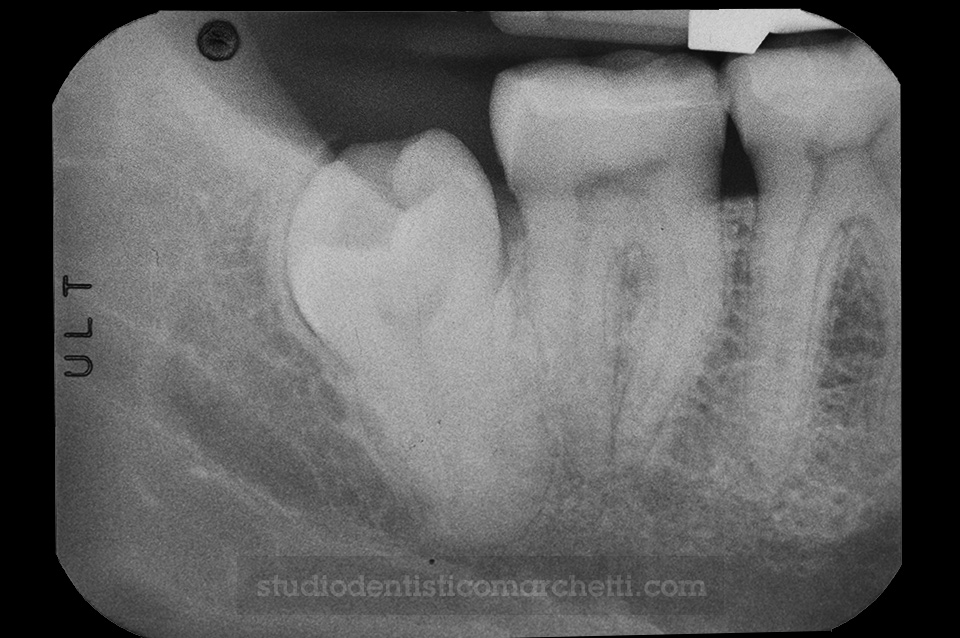

Endodonzia

Ritrattamento Canalare di Molare Affetto da Granuloma

Endodonzia

Ritrattamento Canalare di Molare Affetto da Granuloma